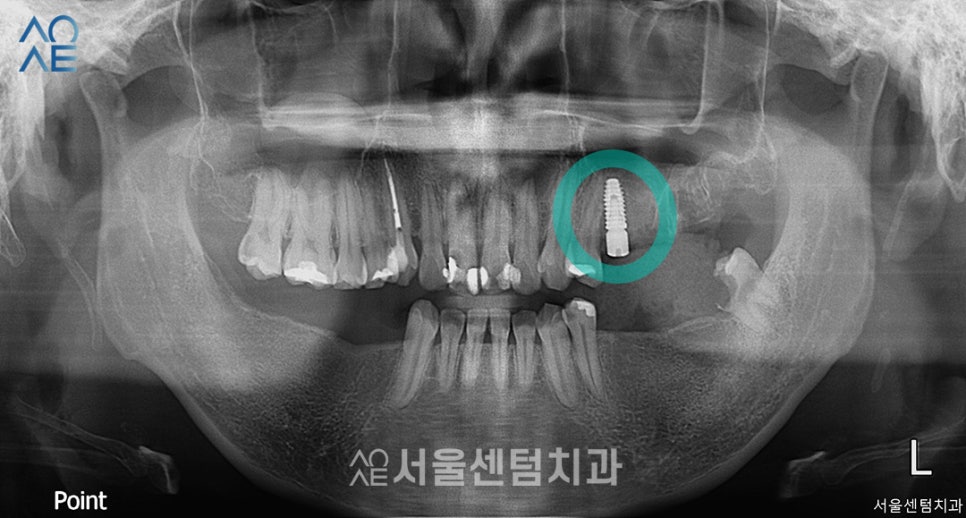

그 다음으로는 오른쪽 아래 어금니에

총 3개의 임플란트를 식립 후

찍은 엑스레이사진입니다.

임플란트는 1차 2차 수술로 나뉘는데

이 분의 경우에는 2차 수술이 필요 없는

일체형으로 식립하였습니다.

2차수술에서는 임플란트의 뿌리를 노출시키는데

일체형의 경우에는 이 과정이 필요 없습니다.

따라서 잇몸이 충분히 아무는 시간을 가진 후

바로 인상채득을 진행하면 됩니다.